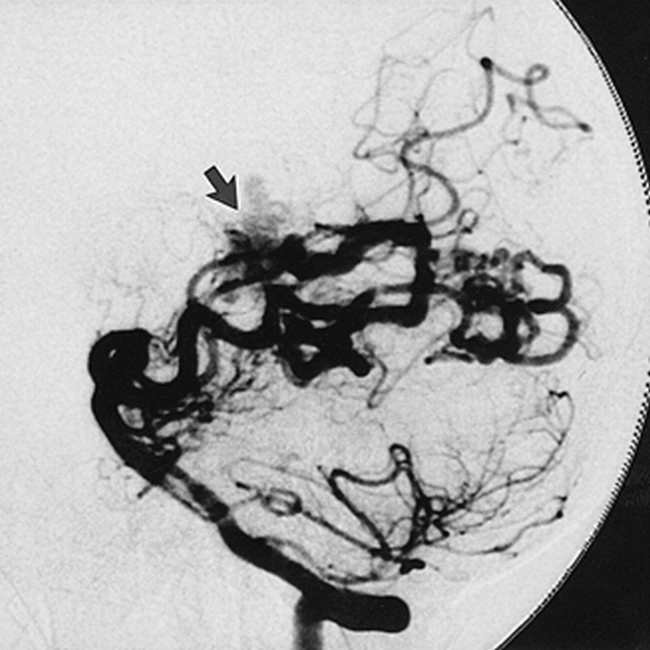

The illustrated case (Figs 1 and 2) is of a 47-year-old woman with a large parenchymal hemorrhage. Diagnostic angiography revealed a left temporoparietal AVM fed through multiple temporal and parietal branches of the posterior and middle cerebral arteries. The vertebrobasilar system used for the subsequent superselective approach was first depicted with biplane angiography (Fig 1). The vertebral angiogram shows AVM supply through temporal branches of the posterior cerebral artery, which are functionally enlarged.

Vertebral injection DSA using Optiray soluble contrast material: lateral view of arterial phase with technique parameters of 86 kVp, 320 mA, 23 milliseconds at 2.5 fps, 10242 × 10 bit images. Arrow indicates AVM